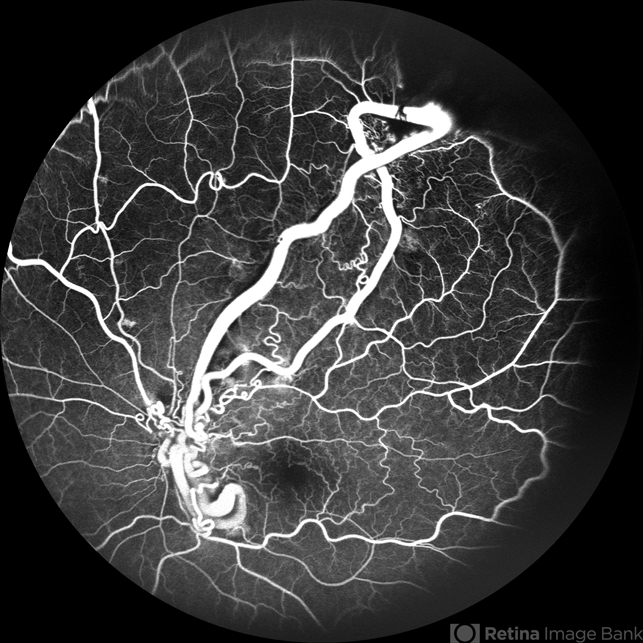

- racemose hemangioma, FFA in a case of Racemose angioma, arteriovenous malformation

Scanning laser ophthalmoscope

mirante - Description

- A case of 10 year old girl with defective vision in LE (6/60) who presented us with this condition.